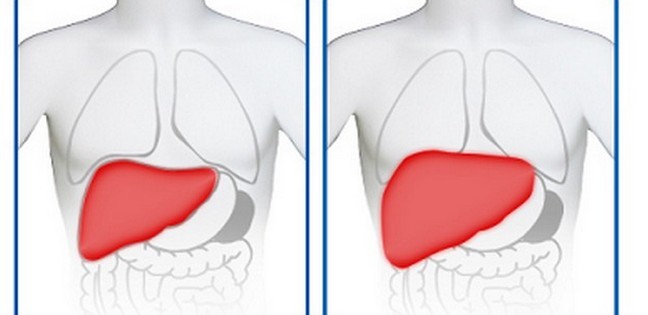

Така складна, на перший погляд, формулювання, як гепатомегалія печінки, передбачає збільшення органу в розмірах. Провокують стан різні захворювання як печінки окремо, так і супутні такому розвитку подій, хвороби. Тобто, гепатомегалія – це не окремий стан, а, швидше, додатковий симптом іншого, основного захворювання. Діагностика гепатомегалії печінки проводиться як за допомогою пальпаторного дослідження (пальпації), так і УЗД, в залежності від форми розвитку і тяжкості трансформацій.

Печінка – самий «терплячий» орган людського організму, який виступає гарантом обміну речовин, фільтром потрапляють в організм продуктів, а також нейтралізатором отруйних токсинів і отрут. На тлі збою даних важливих для життєдіяльності процесів, відбувається зміна стану здоров’я і, як наслідок, можливе збільшення печінки. І навіть, незважаючи на те, що орган має величезні регенеративні здібності, даний стан може означати ймовірну небезпеку для нього. Особливо часто діагностується гепатомегалія органу при зловживанні алкоголем чи, у разі, якщо, внаслідок неправильного харчування, розвивається жировий гепатоз.

Тим не менш, гепатомегалія (збільшення печінки) – це цілком оборотний процес, за умови, що у тканинах органу немає циррозивных або гепатокарциномных змін. Але для визначення точного прогнозу патології необхідно якомога швидше звернутися за лікарською допомогою.

Невираженою формі характерно збільшення печінки на 1, максимум 2 див. В цьому разі причин турбуватися немає, можливо, викликали цей стан згубні звички або неправильне харчування. Відчувається незначне збільшення печінки, як легке нездужання і слабке зниження апетиту, можуть також з’явитися дискомфорт у животі, шкірний свербіж та печія. При пальпації змін можна і не помітити. Основне лікування періоду полягає у виключення шкідливих звичок і налагодженні правильної схеми живлення.

Симптоми другій стадії аналогічні, за винятком посиленою болі в правому підребер’ї. Відчуття можна описати, як тягнуть, розпираючий, шлунок погано перетравлює їжу, в його області відчувається тяжкість. При пальпації збільшений орган відчувається більш чітко. Причини можуть бути схожими з провокаторами стану в першому випадку, проте також спонукати збільшення печінки в стані захворювання.

Останню стадію визначають навіть візуально, без пальпації, оскільки із-за значного збільшення печінки деформується шкірний покрив, і права область живота виступає над іншими областями. Внутрішні органи зміщуються, їх робота стає порушеною. Печінка, при цьому в змозі займати як половину, так і більшу частину черевного простору. Симптоми характеризуються постійним наростанням і досягненням апогею: сильний біль, сильна нудота, багаторазова блювота, сильний свербіж і виражена жовтушність шкірних покривів.